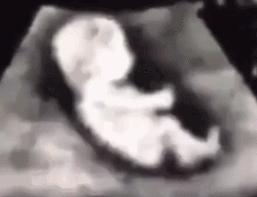

您描述自己的月经周期规律为28天,在末次月经后20天时服用奥利司他胶囊1粒,而该药彻底排出(粪便和尿液)需要 3~5 天,即您在“不敏感期”服用奥利司他,且只服用了1粒,这个时期的用药符合上述所说的“全或无”理论,如您的B超无异常,且没有阴道出血等异常表现,是可以继续妊娠的。